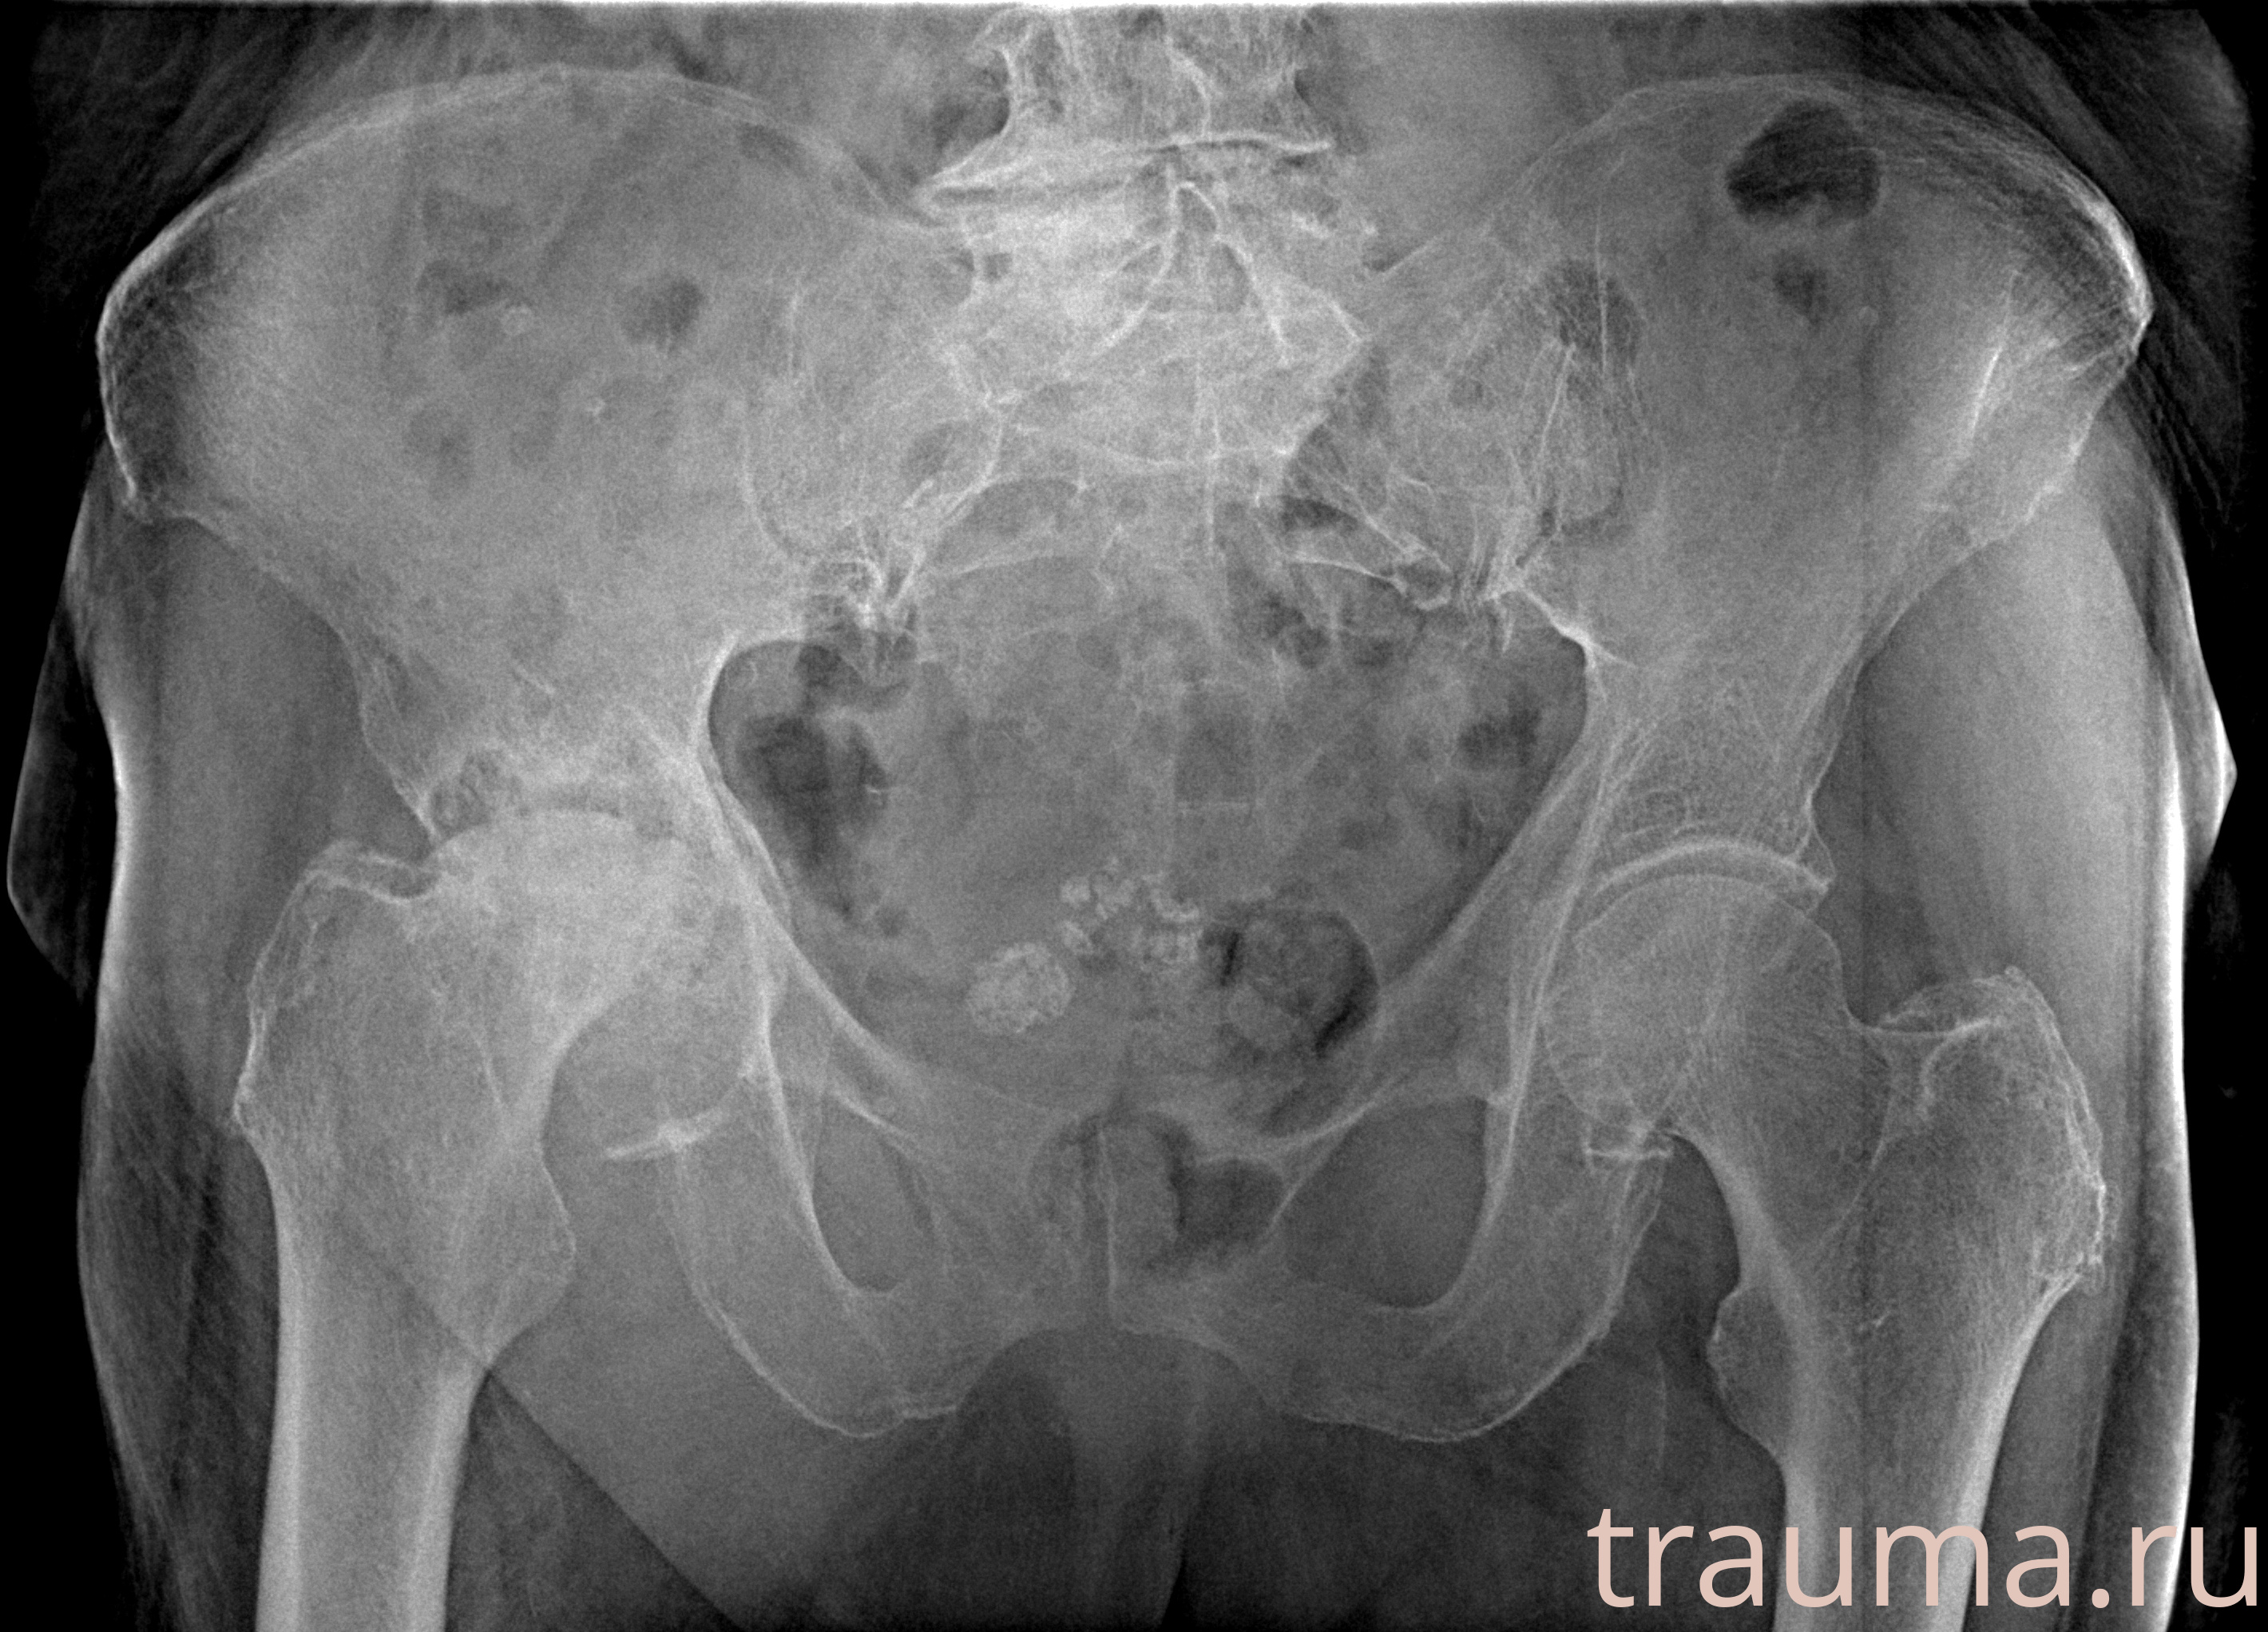

Рентген на дому: по вашему адресу приезжает врач-рентгенолог, травматолог-ортопед с мобильным рентгеновским аппаратом, проводит диагностику травмы или заболевания, делает необходимые рентгенограммы, дает рекомендации по дальнейшему лечению. Получить качественные снимки в домашних условиях возможно благодаря уникальной методике, разработанной МосРентген Центром для института  Склифосовского